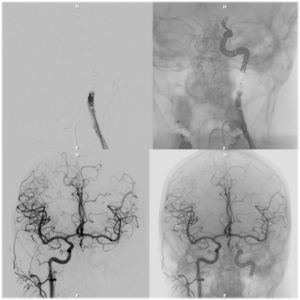

Nose bleeding (or epistaxis) is a not uncommonmedical condition that can occasionally become serious when it is refractory to conservative medical treatments. When conservativemaneuvers, including anterior and posterior packing of the nasal cavity, are unsuccessful at controlling the bleeding, interruption of the blood supply to the sinonasal area can be performed, either by surgical ligation or by transarterial embolization. The procedure involves diagnostic angiography with meticulous attention to the collateral pathways between the extra-cranial, orbital, and intra-cranial circulation followed by the injection of small particles through microcatheter into the tiny arteries that supply blood flow to the back of the nose.

Tumor embolization is a nonsurgical, minimally invasive procedure performed by interventional radiologists andinterventionalneuroradiologists. It involves the selective occlusion of blood vessels by purposely introducing emboli, in other words deliberately blocking a blood vessel. In the setting of tumors of the head and neck, embolization can be performed preoperatively to reduce the amount of bleeding that may occur during surgery. Highly vascular tumors, such as glomus tumors, paragangliomas, meningiomas, and metastatic renal/lung/breast/melanoma/renal cell carcinomas are a few examples of tumors that are amenable to preoperative embolization.

There are aggressively behaving tumors and infections and even post-traumatic and post-surgical situations that may occur that may result in exsanguination if not treated by the deliberate sacrifice or occlusion of the at risk blood vessel. Because the cerebral circulation has built in redundancies (or connections) between the front and back and right and left, such deliberate sacrifice may result in no long term negative consequence for the patient. The parent artery sacrifice procedure involves the deliberate occlusion of one of the carotid or vertebral arteries by deployment of numerous coils and/or vascular plugs into the blood vessel lumen until complete obstruction of flow is achieved.